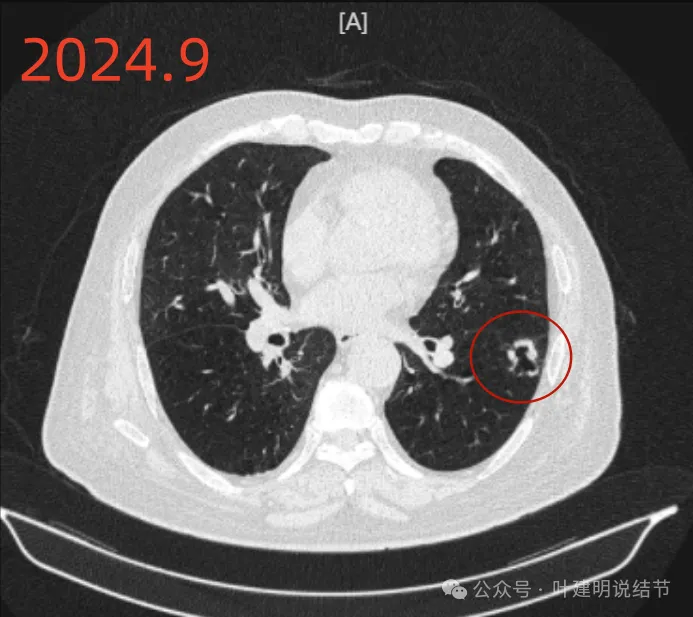

再看2024年9月时的影像:

病灶出现,紧贴叶间裂,有小血管走向病灶侧。

中间有空腔,叶裂侧实性并牵拉叶间裂。

囊腔灶、轮廓清、小血管进入囊壁、囊壁厚薄不均、叶间胸膜牵拉。

表面不平、混合密度、囊腔壁厚薄不均、内壁不光滑、有细支气管扩张通气征。

明显壁厚薄不均的囊腔灶,囊壁基本实性,表面不平,内壁不光滑,且邻近叶间裂并牵拉叶裂。

前后最明显层面对比:

间隔才三个月,明显感觉更不舒服,更像恶性了些。